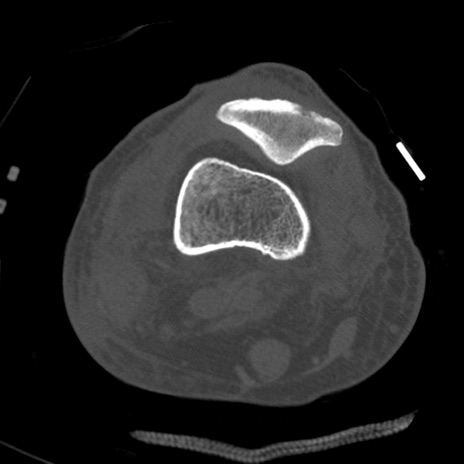

症例28 右膝関節CT(横断像)

右膝関節CT